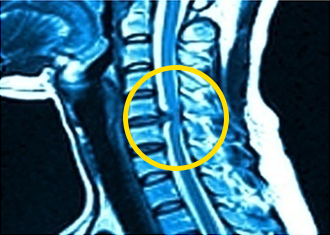

목디스크 증상 [초기증상]

목디스크는 허리디스크와 마찬가지로 파편이 튀어나와서 신경을 누르는 질환 중 하나입니다. 정확한 명칭이 있는데 경추 추간판 탈출증이라고 하네요. 이는 허리디스크보다는 작다고 하더라도 추간판 탈출증의 모양 및 원리가 비슷하다고 할 수 있다고 합니다.

목디스크 증상은 디스크의 겉면이라고 하는 섬유륜이 찢어짐과 함께 안쪽 수핵이라는 것이 튀어나와서 신경을 누르게 되어 나타나게 되는데요. 경추의 신경이 뇌에서 바로 이어지는 신경이기 때문에 디스크가 누르게 되면 어깨에도 통증이 나타날 수 있고 팔이 저린 증상이 나타날 수도 있는 것이라고 합니다. 심한 경우 경추 척추 신경의 압박은 사지가 마비될 수도 있기 때문에 주의가 필요합니다.